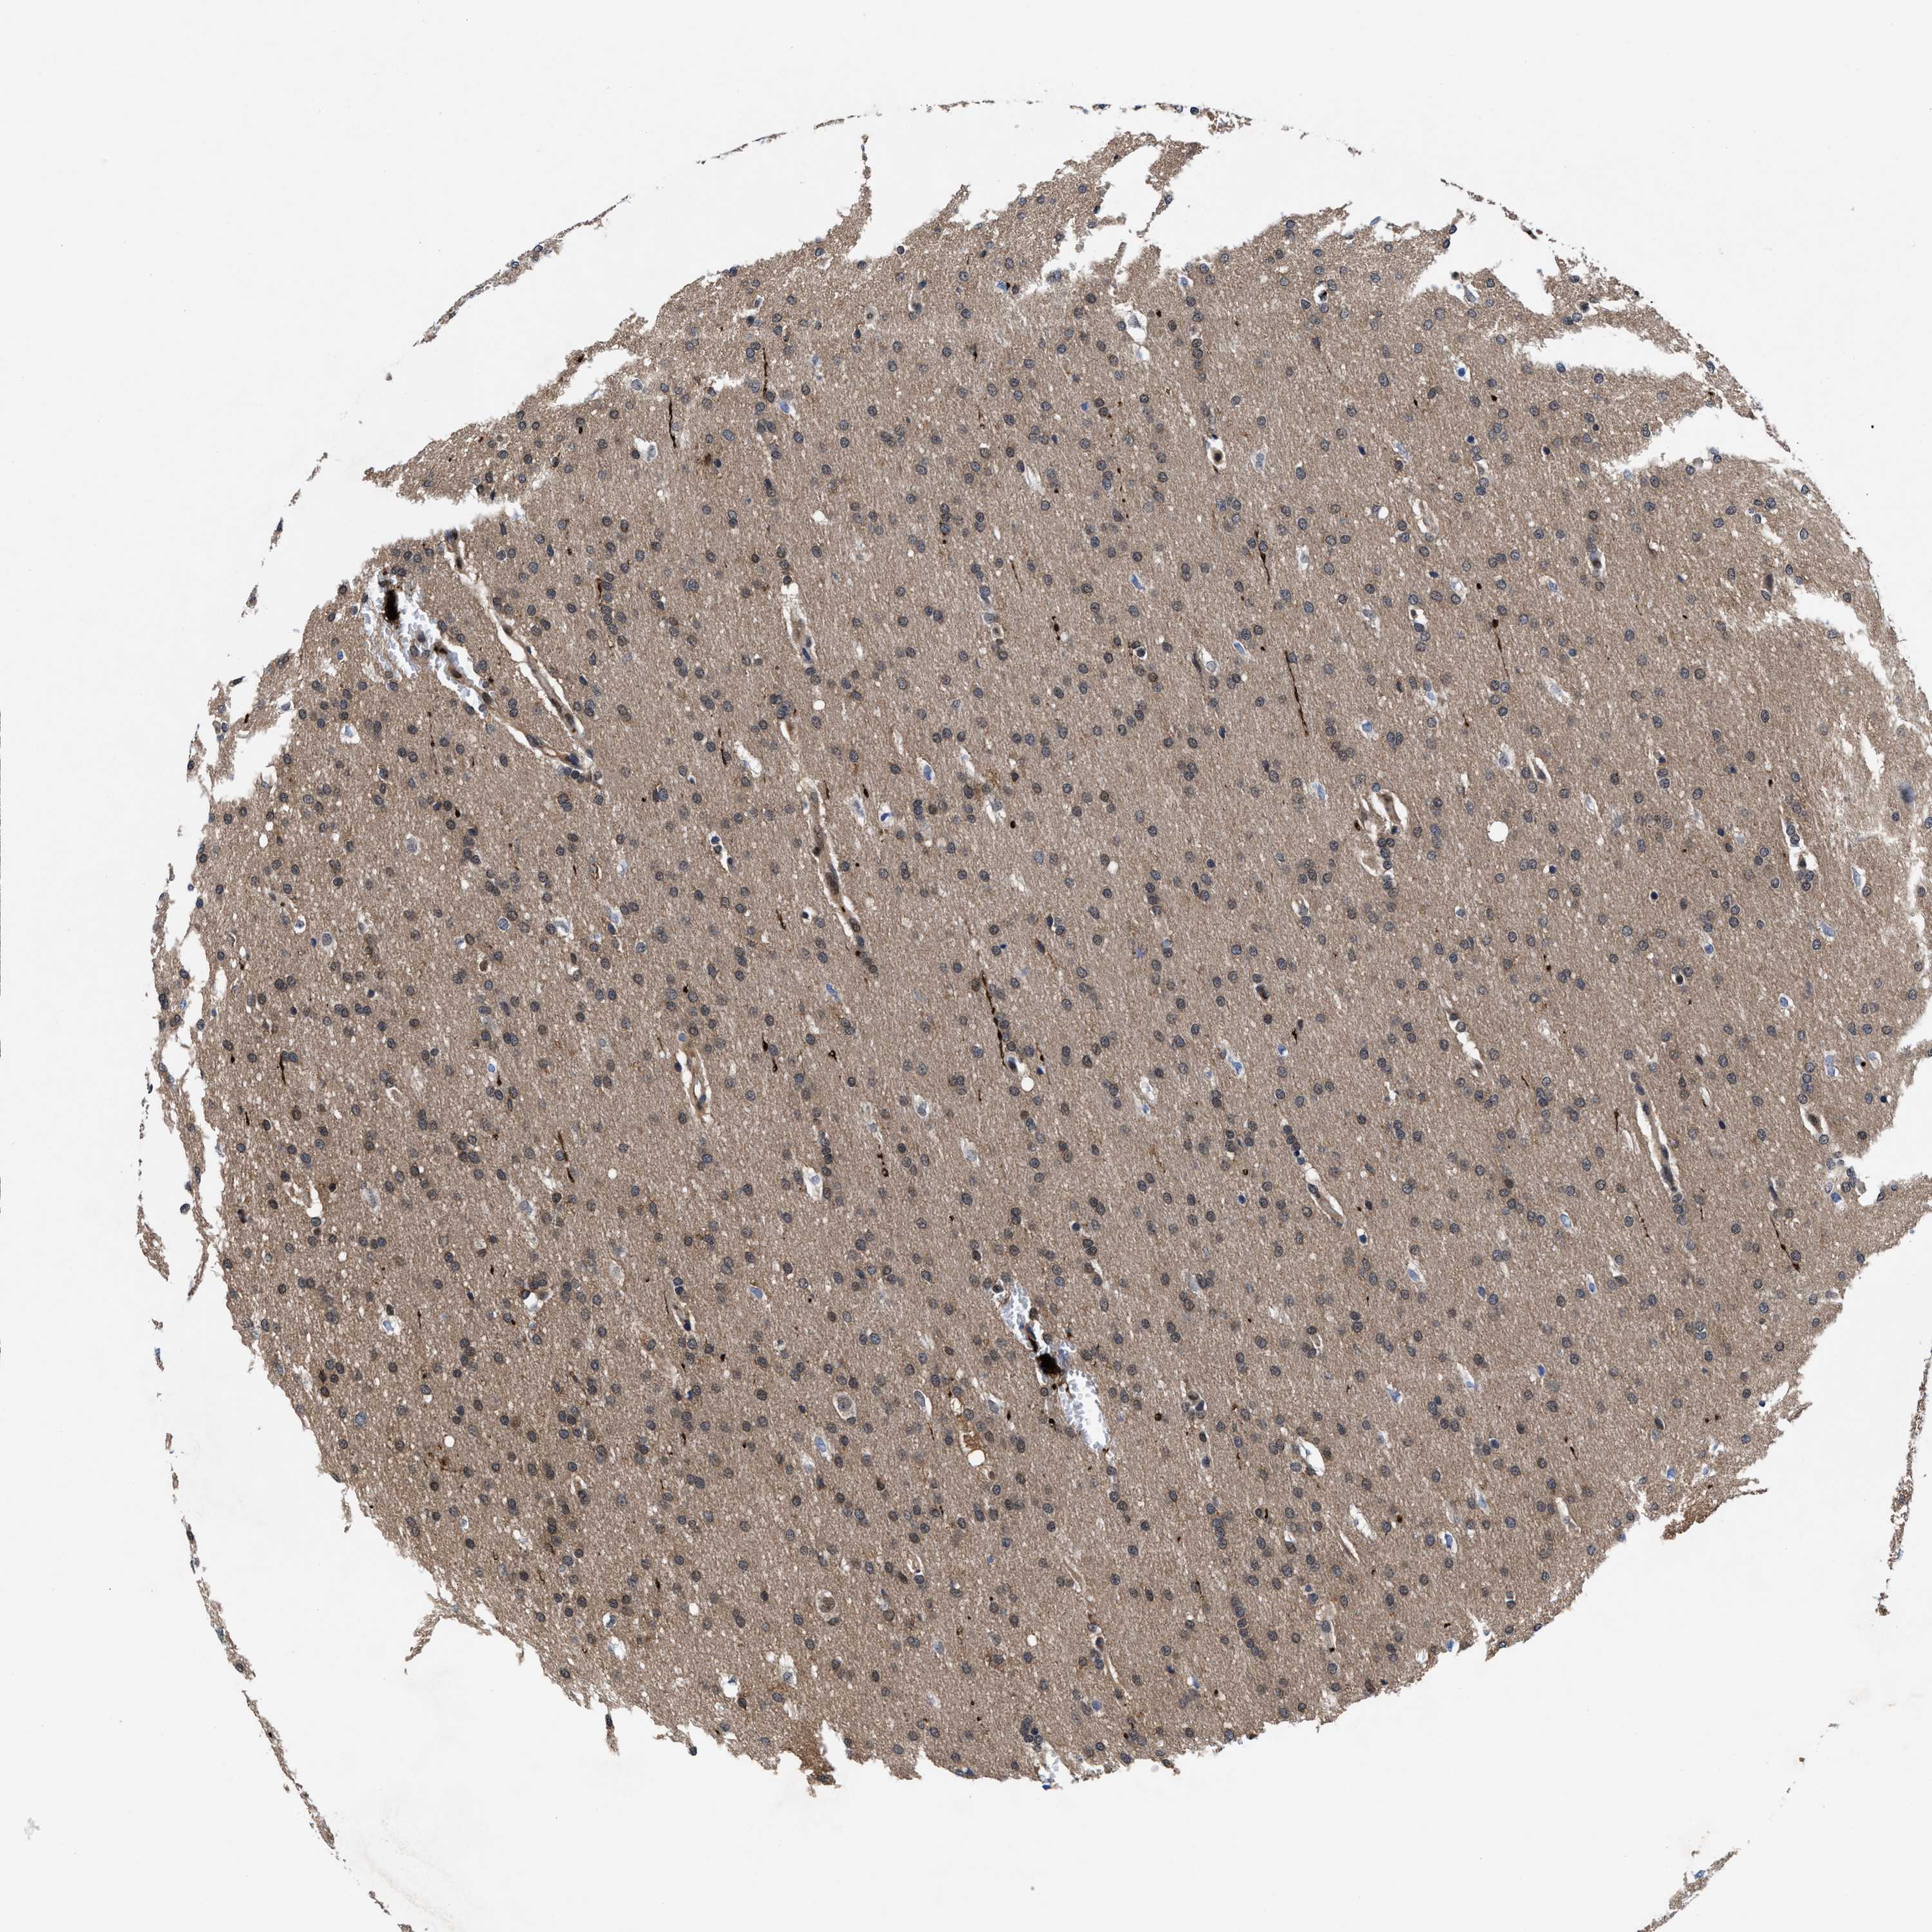

GLIOMA - Protein expressioni

A mouse-over function shows sample information and annotation data. Click on an image to view it in a full screen mode. Samples can be filtered based on level of antibody staining by selecting one or several of the following categories: high, medium, low and not detected. The assay and annotation is described here.

Note that samples used for immunohistochemistry by the Human Protein Atlas do not correspond to samples in the TCGA dataset.

Antibody stainingi

Antibody staining in the annotated cell types in the current human tissue is reported as not detected, low, medium, or high, based on conventional immunohistochemistry profiling in selected tissues. This score is based on the combination of the staining intensity and fraction of stained cells.

Each image is clickable and will lead to virtual microscopy that enables deeper exploration of all samples and also displays staining intensity scores, fraction scores and subcellular localization as well as patient and tissue information for each sample.

HPA022434

HPA022953

HPA022959

HPA028758

CAB007783

Glioma, malignant, High grade

Glioma, malignant, Low grade

Glioblastoma, NOS